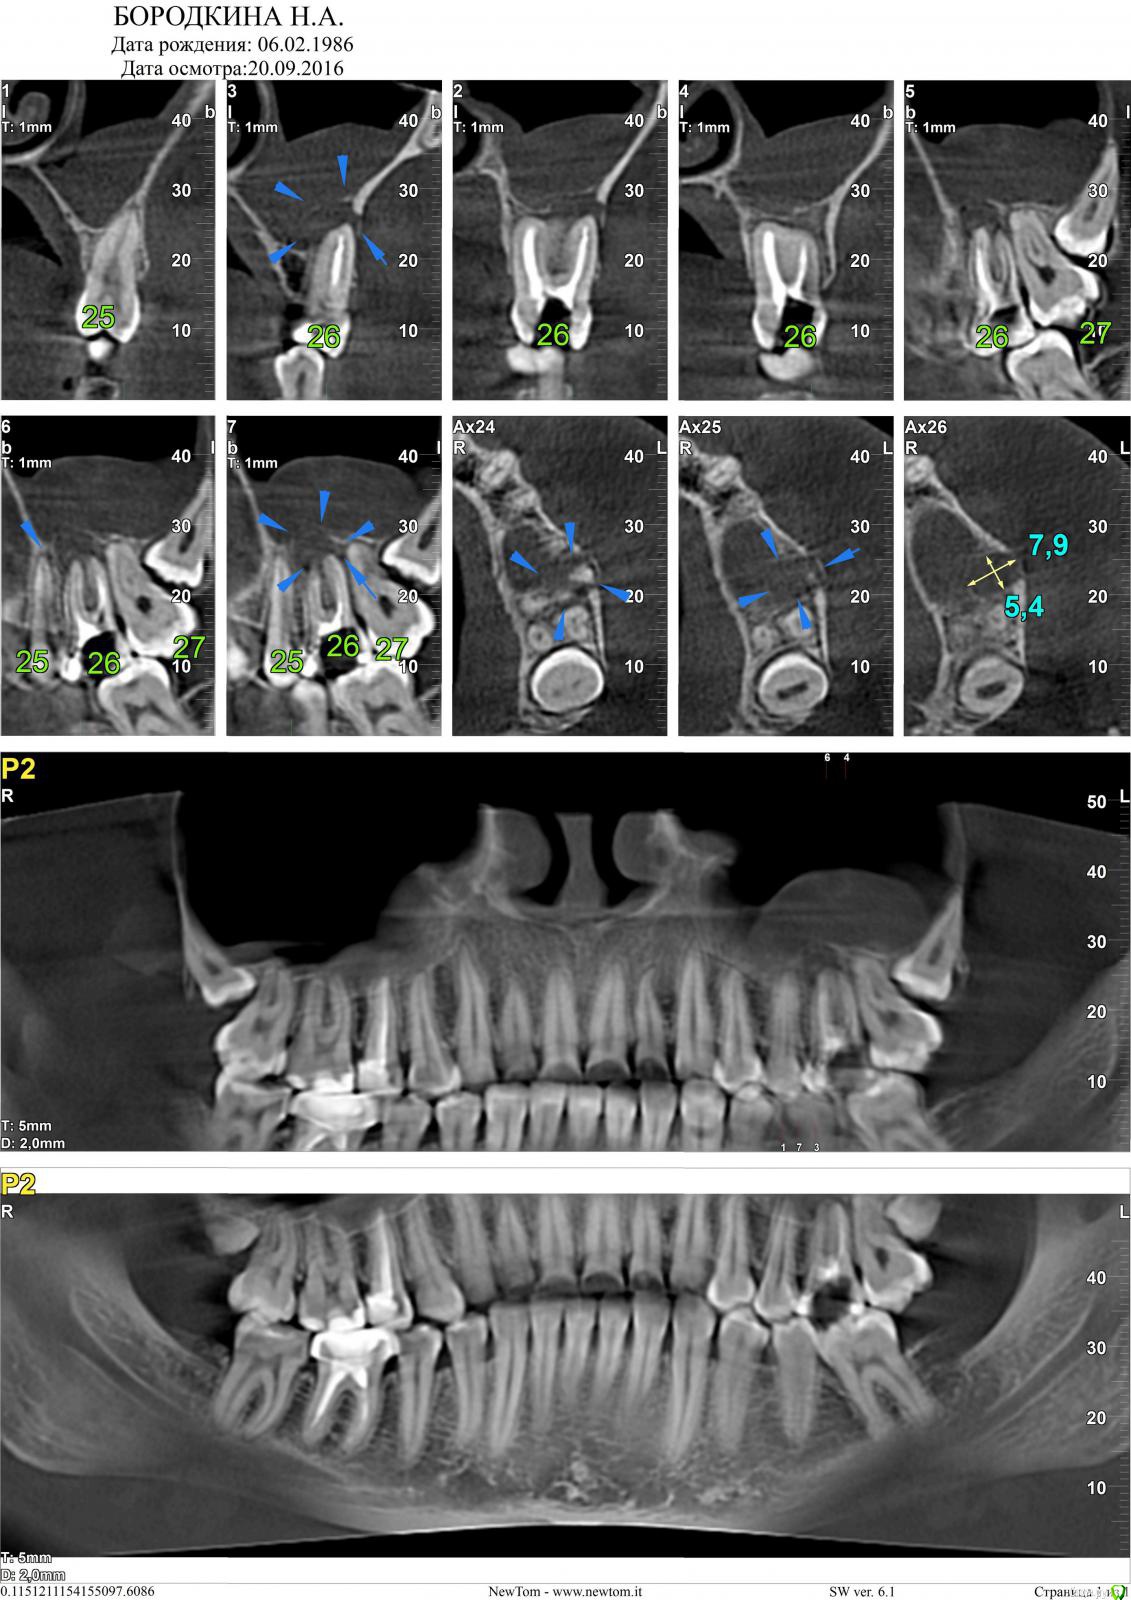

korsa Опубликовано 5 октября, 2016 Поделиться Опубликовано 5 октября, 2016 Всем добрый вечер, прошу помощи. Давным давно, уже и не помню где и кто делал, был удален нерв и запломбирован зуб. 3 недели назад обратилась к врачу с острой болью, не могу наступать, на горячее/холодное реакции нет. Терапевт не смогла вскрыть запломбированный канал и отправила в другую клинику. В другой, мне не стали вскрывать канал(почему не могу сказать, пазухи близко, наговорила мне что-то, для меня не ясное), выписала антибиотики и отпустила, сказав явиться через день. На следующий день зубная боль прошла, но случился сильный отек. На повторном приеме отправила меня к хирургу, та удивилась что канал не вскрыли при первом обращении. В общем, хирург поставила дренаж и отпустила. На 3 день, дренаж сняли, отправили на КТ. После КТ хирург сказала искать врача и попробовать лечить. Но т.к. я простыла, лечение отложилось на 10 дней. После выздоровления, я записалась на консультацию к другому хирургу... Проснувшись в день записи обнаружила снова отек щеки, не такой сильный как в первый раз, но отек(Помогите определить, пожалуйста, действительно он под удаление или все же можно спасти, зуб жевательный, да и вообще, со своим не хотелось бы расставаться(((Первый снимок от 20.09.16И еще, что за потемнение над зубом, такое обширное(под красной линией)Зуб - 26.Второй 14.02.15 - на нем то вообще ни чего нет. Ссылка на комментарий

St. Опубликовано 5 октября, 2016 Поделиться Опубликовано 5 октября, 2016 И еще, что за потемнение над зубом, такое обширное(под красной линией) Реакция слизистой оболочки гайморовой пазухи на хроническое воспаление от 26 зуба Ссылка на комментарий

korsa Опубликовано 6 октября, 2016 Автор Поделиться Опубликовано 6 октября, 2016 Всем большое спасибо! Еще пару вопросов Нужна ревизия каналов. Я сейчас пью антибиотики, и припухлость еще не спала, на ревизию когда можно записываться, прям сейчас, или пропить курс антибиотиков? Реакция слизистой оболочки гайморовой пазухи на хроническое воспаление от 26 зуба Скажите, а причин беспокоиться за пазуху и посещать ЛОРа нет необходимости? Ссылка на комментарий

DmitrySH Опубликовано 6 октября, 2016 Поделиться Опубликовано 6 октября, 2016 Я сейчас пью антибиотики, и припухлость еще не спала, на ревизию когда можно записываться, прям сейчас, или пропить курс антибиотиков?Скажите, а причин беспокоиться за пазуху и посещать ЛОРа нет необходимости? Ждать не стоит, надо лечением заниматьсяЛор не поможет, причина в зубе. 1 Ссылка на комментарий